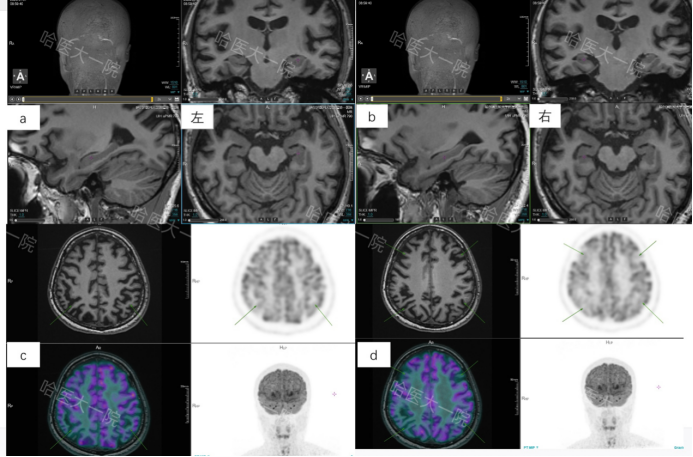

经过核医学科医师图像判读sMRI显示脑萎缩,双侧内嗅皮层、海马及杏仁体萎缩,同机18F-FDG显像双侧颞顶联合区、后扣带回及额叶伴葡糖糖代谢对称性减低,sMRI及18F-FDG显像不符合额颞痴呆典型影像表现;为近一步确诊行18F-AV45及18F-AV1451显像,二者显像均为阳性,综合患者sMRI及多探针联合成像结果为患者明确病因诊断,即认知及情绪障碍致病来源为早发阿尔兹海默症,并协助临床进一步制定治疗用药方案,同时18F-AV1451为患者日后治疗效果评估提供了影像基线。